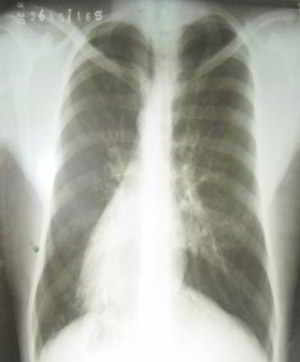

Figura 1